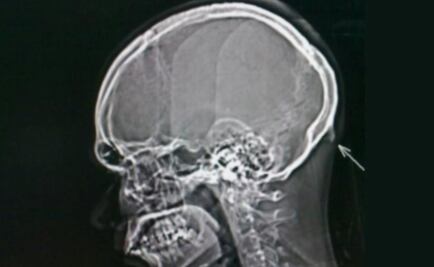

Uso de celulares provocaría crecimiento de “cuerno” en las personas

Un grupo de científicos de la Universidad de Sunshine Coast, en Australia, descubrió que el uso de smartphones está provocando el crecimiento de una especie de “cuerno” en el cráneo humano